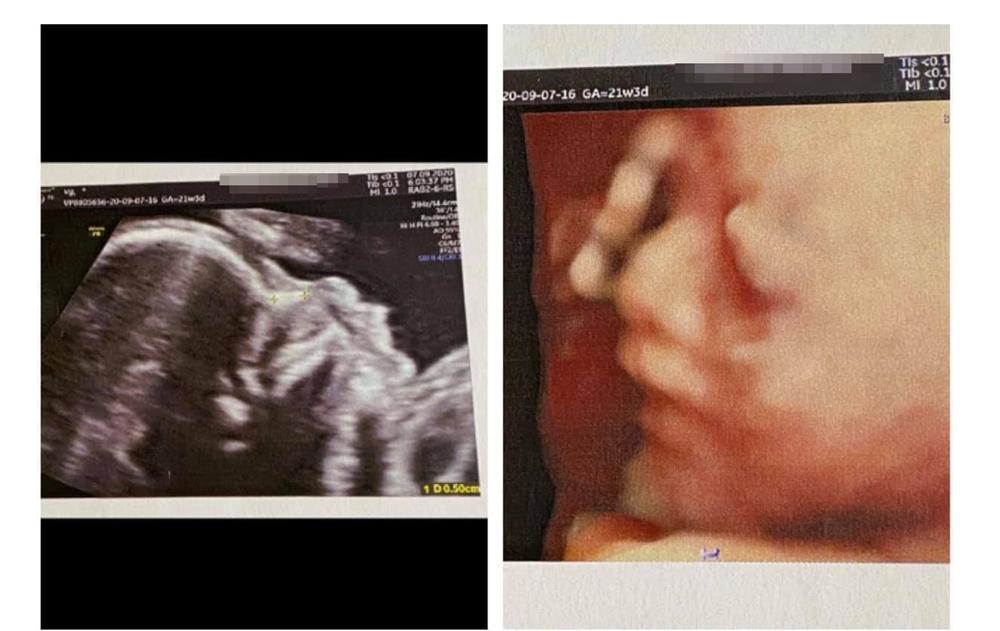

Hôm qua nhân ngày Phụ nữ Việt Nam (20/10), Vy Pumpe tiếp tục gây chú ý khi khoe hình ảnh siêu âm đầu tiên về thai nhi trên mạng xã hội.

Đính kèm hình ảnh, bạn gái Mạc Văn Khoa hạnh phúc chia sẻ: "Năm nay 20/10 mẹ có quà siêu to, siêu khủng, siêu vô giá luôn. Chào con gái yêu 'Minnie' của bố mẹ. Nôn nao được cắn cái bản mặt này quá".

Bạn gái Mạc Văn Khoa khoe hình siêu âm con.